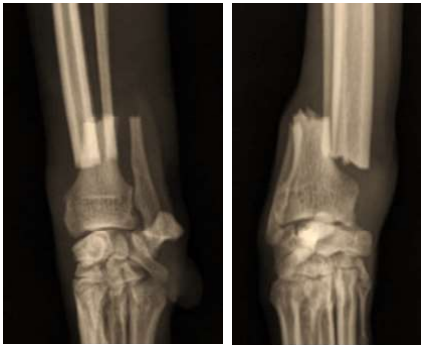

As radiografias abaixo pertencem a um Fox Terrier de 17 semanas de idade e evidenciam uma fratura distal da tíbia. Trata-se de uma fratura fechada, que se estende por três quartos da linha fisária tibial, prolongando-se até a metáfise lateral da tíbia:

Enunciado 4939636-1

A fratura não apresenta comunicação com a superfície articular. Com base nessa descrição, qual das seguintes opções melhor classifica essa fratura?